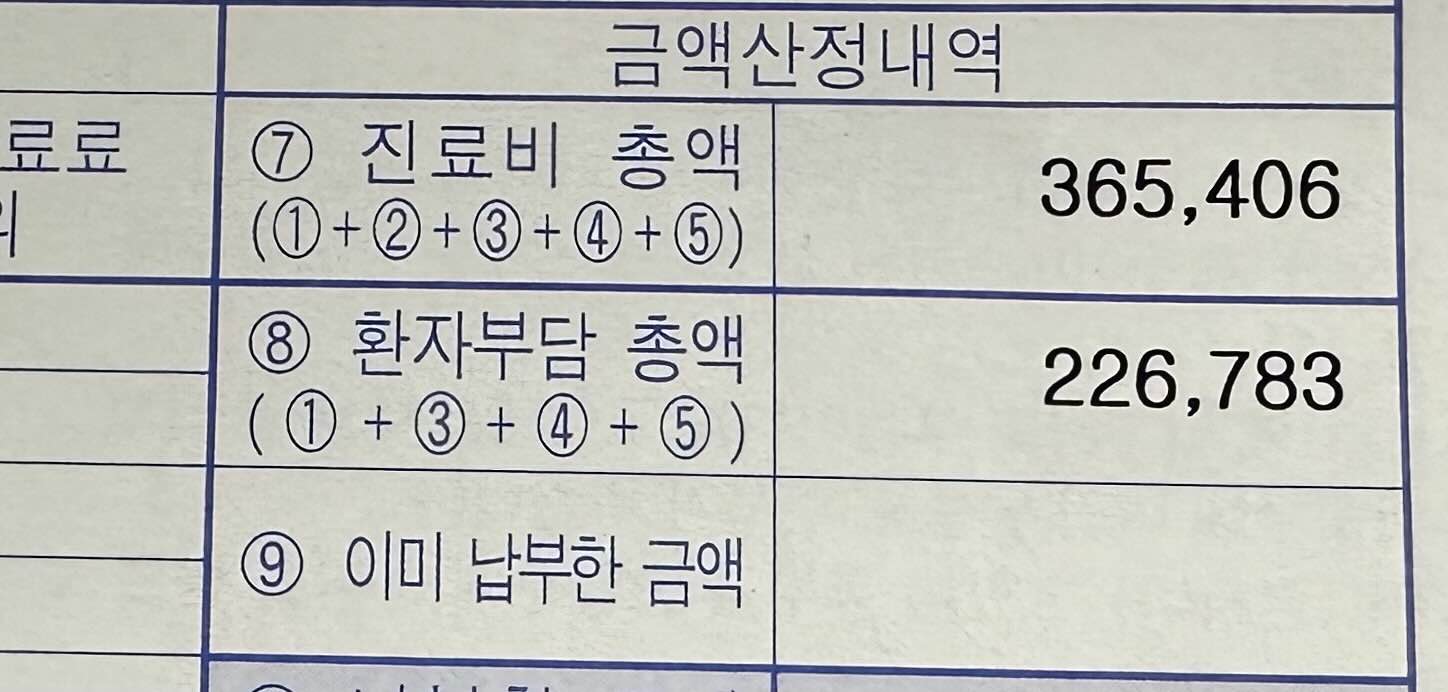

5. 고막환기관 삽입 수술의 세부내역서 입니다. 저는 양쪽 귀에 한 개씩 총 2개를 넣었습니다. 참고해 주세요.

진료비 총액에서 환자부담총액만 내면 되기때문에 저는 226,783원을 내었습니다. 사실 수술비용이나 진료비용의 경우에는 병원에 따라 다르기 때문에 이 가격이 정답이라 할 수는 없지만 그래도 금액이 엄청 많이 나오지 않는다는 사실 정도는 알 수 있는 것 같아요.